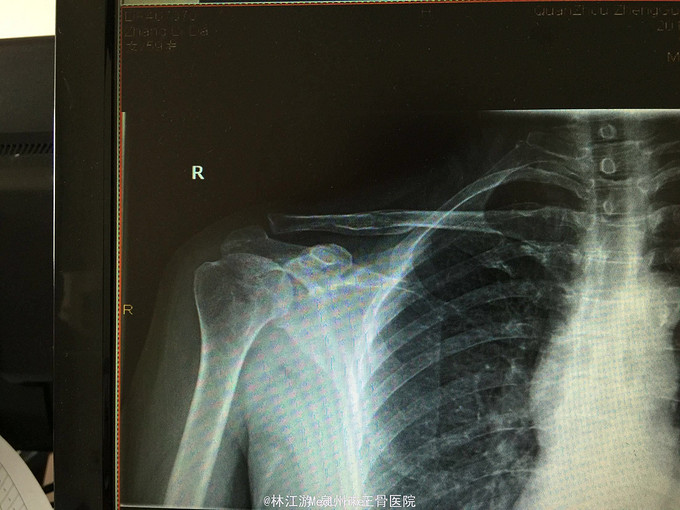

右锁骨粉碎性骨折闭合复位克氏针内固定术

术后三年取内固定物,肢体活动正常